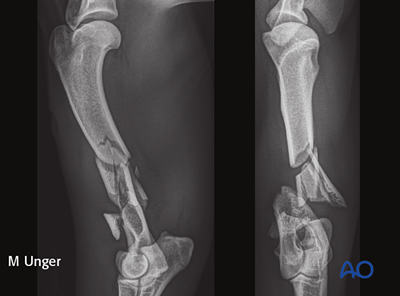

More than 200 original illustrations accompany the step-by-step descriptions of the various fixation techniques and approaches. Furthermore, to help identify the fractures, x-rays of almost all fracture types are included in the material.

Most treatments include a case with preoperative, postoperative, and follow-up x-rays.